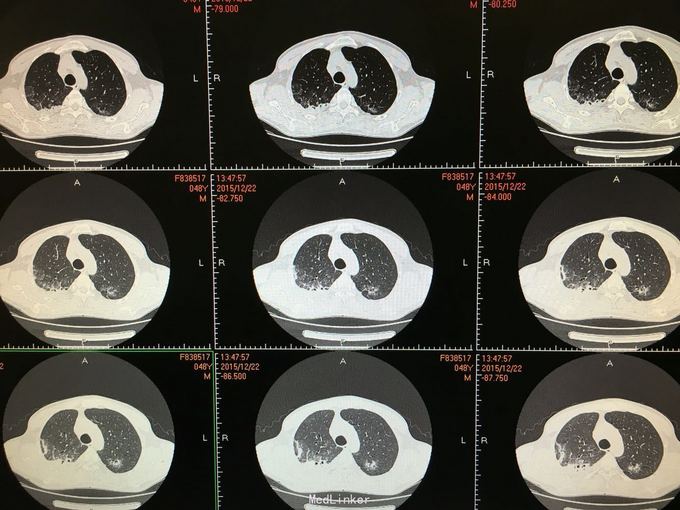

间断咳嗽咳痰5月余。患者缘于半年前确诊为骨髓增生异常综合征,并行造血干细胞移植术。术后出现发热,完善相关检查考虑为肺部真菌感染,给予抗感染治疗后体温正常,病情好转出院。出院后仍有间断咳嗽咳痰,咳黄色痰,无发热,自行口服伏立康唑200mg,2/日治疗,12月初复查CT提示双肺病灶较前进展,右肺中叶新增病灶。

根据症状体征及辅助检查,结合病史考虑真菌感染可能性大。进一步气管镜检查,结果如下。组织活检标本可见。病理回报提示真菌团,培养见曲霉菌生长。明确诊断后给予两性霉素B雾化吸入及伏立康唑静脉应用抗真菌治疗,同时给予环孢素口服。

造血干细胞移植后肺部感染常见,其中以曲霉、卡肺等多见,患者经气管镜检查已将真菌团块取出。术后给予监护,口服云南白药、垂体后叶素雾化止血等治疗,无明显出血,症状逐渐好转。复查CT也明显好转。